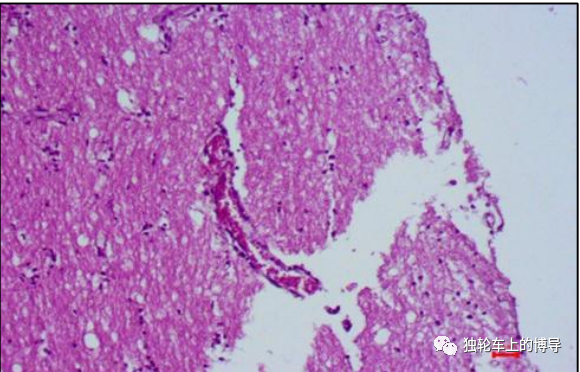

神经节神经元中发现了各种大小的卵圆形胞浆内嗜酸性包涵体(negri小体

在神经细胞浆 内增殖,形成嗜酸性包涵体-内基小体 (negri body)

内基体negri body见于狂犬病患者神经元中,尤其是大型神经元如海马

在组织病理学检查中,内基氏小体(negri bodies)通常出现在狗的海马中